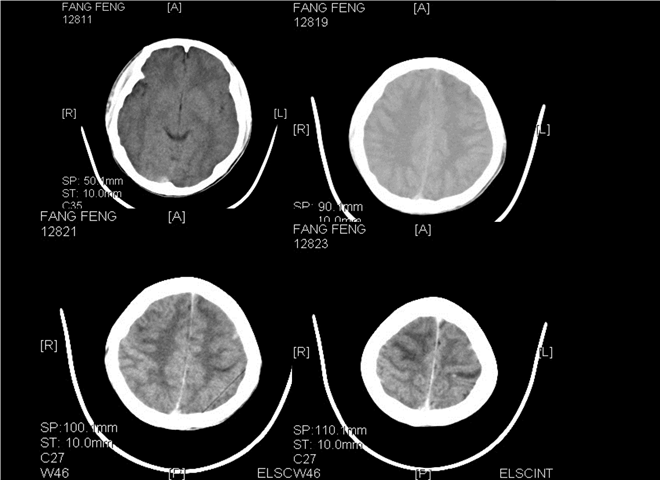

13_CT增强扫描